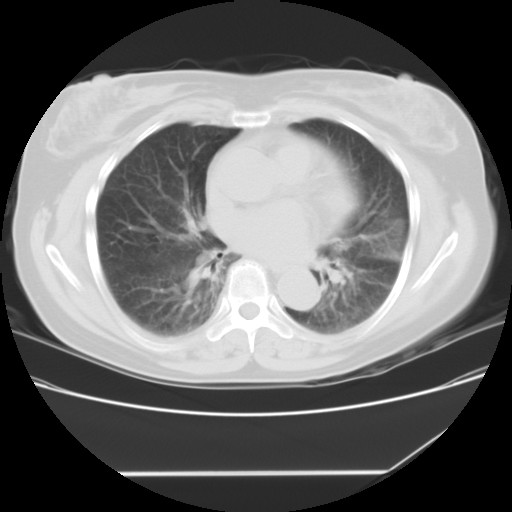

标题: CT24018:女性,62岁,咳嗽4年,无热,胸部CT扫 [打印本页]

女性,62岁,长期咳嗽,既往从事工作有粉尘接触,有高血压病史,110/150mmhg,近日咳嗽加重,脸面浮肿,请大家帮看下,

1、尘肺;2、慢性支气管炎合并肺部感染;3、心影增大(左房、左室大),考虑高血压性心脏病。

慢支并肺部炎症;右肺结核球?主肺动脉、右肺动脉影不宽,右心室不大,不支持肺心病;无心包积液。

间质性肺炎,有纤维化趋势。

1)慢性支气管炎并肺部感染、肺气肿。2)肺间质纤维化。

间质性肺炎,左下肺机化性肺炎。